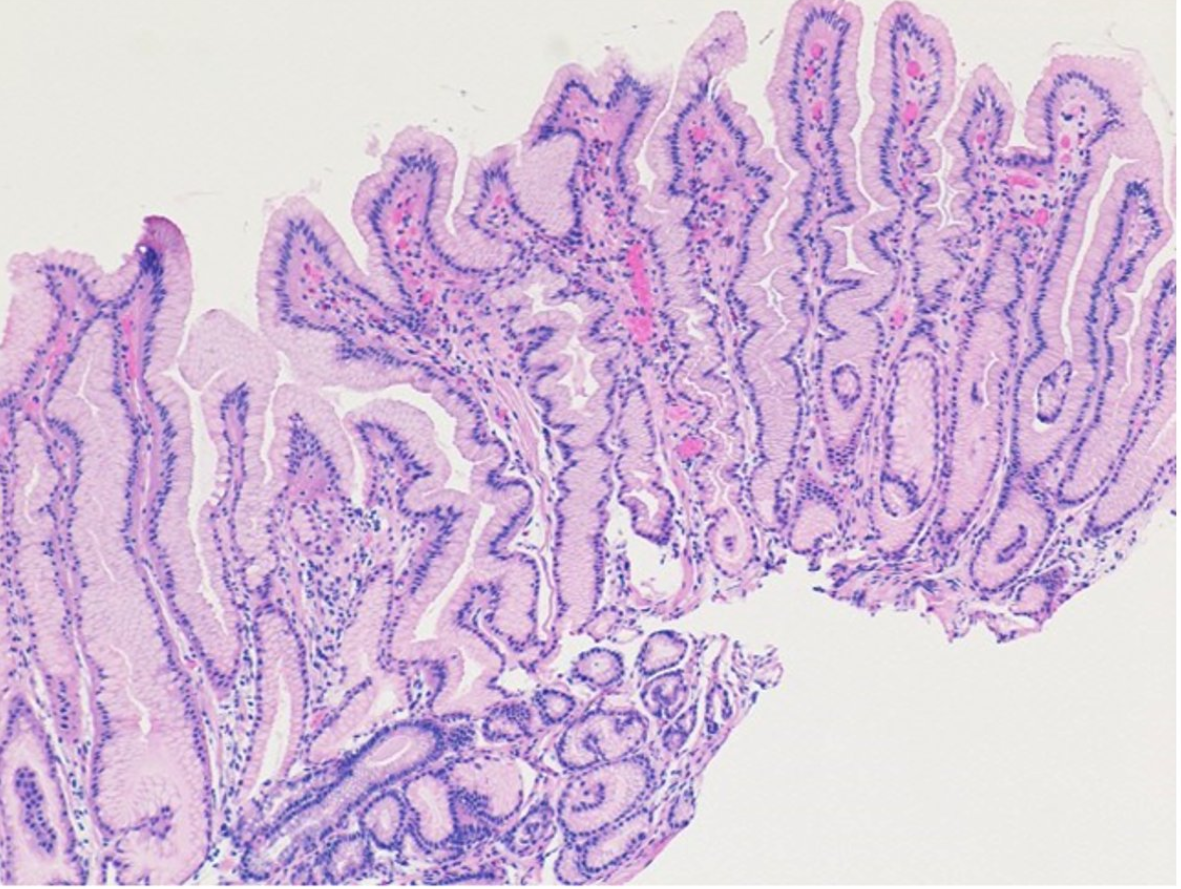

Recently, JPGN’s twitter feed shared the images below from a recent report (SJ Pathak et al. JPGN January 2022 – Volume 74 – Issue 1 – p e16doi: 10.1097/MPG.0000000000003276. Menetrier Disease in a Pediatric Patient With Ulcerative Colitis and Primary Sclerosing Cholangitis)

Related blog post: Image Only: Pediatric Menetrier’s Disease